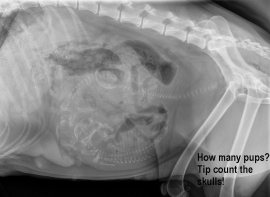

Bing is an 8 year old Siamese cat who loves nothing more than a day filled with adventures followed by an evening of fussing. Unfortunately his exploring instincts landed him in trouble recently when he was hit by a car whilst dashing across the country lane near where he lives. Thankfully his owners were quickly on the scene and rushed him over to Oak Barn Vets for treatment.